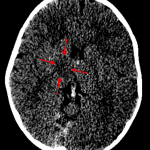

- High attenuation within the superior and posterior aspects of the superior sagittal sinus and in the straight sinus and bilateral internal cerebral veins

- Additional focus of high density near the left cerebellar tentorium

- Area of hypoattenuation in the right thalamus and genu of the right internal capsule

- Dural and deep venous sinus thrombosis

High attenuation within the superior and posterior aspects of the superior sagittal sinus and along the straight sinus and bilateral internal cerebral veins concerning for dural and deep venous sinus thrombosis. Additional focus of high density near the left cerebellar tentorium likely represents thrombus in the left transverse sinus. Recommend brain MRI with and without contrast for further evaluation.

Area of hypoattenuation in the right thalamus and genu of the right internal capsule is concerning for edema and possible developing venous infarct. This can also be assessed with MRI.

No acute hemorrhage, mass effect, or hydrocephalus.